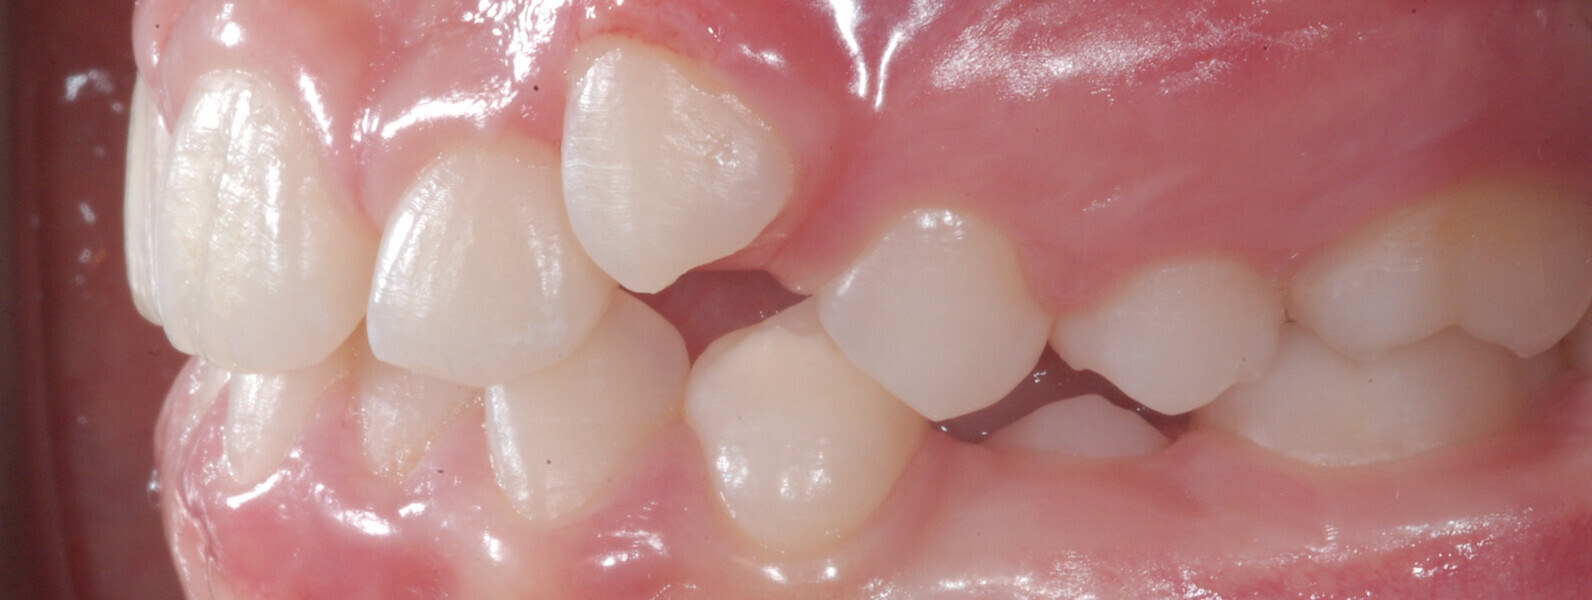

A 14-year-old female patient presented with the chief complaint of midline deviation and dental crowding in both arches. Facial analysis showed a hypodivergent growth pattern, a normal nasolabial angle, a harmonious profile and proper chin projection. Clinical examination revealed a Class III skeletal relationship (ANB = 0°) and Class I molar relationship. The maxillary right canine was absent, and this had led to space loss and mesial drift of posterior teeth on the right side, resulting in a slight Class II molar relationship. The maxillary left canine had erupted in a high position. The mandibular arch displayed crowding despite the agenesis of the right second premolar and the persistence of the primary molar (Figs. 3–11). The radiograph showed the probably premature loss of the maxillary right primary canine and consequently impacted maxillary right permanent canine, and the agenesis of the mandibular right second premolar and the mandibular right third molar (Fig. 12).

Fig. 4